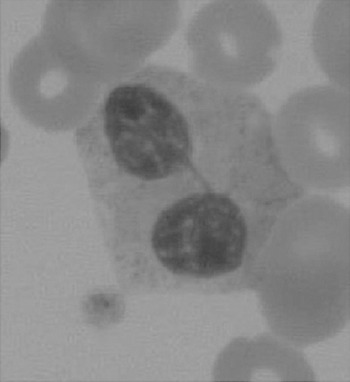

The haematologist will see multiple changes on the blood films. One such example is shown in Figure 7.4.

Neutrophilia, monocytosis and lymphopenia are common findings, especially during acute exacerbations of septic episodes. The white cells are often affected by the drugs being administered.